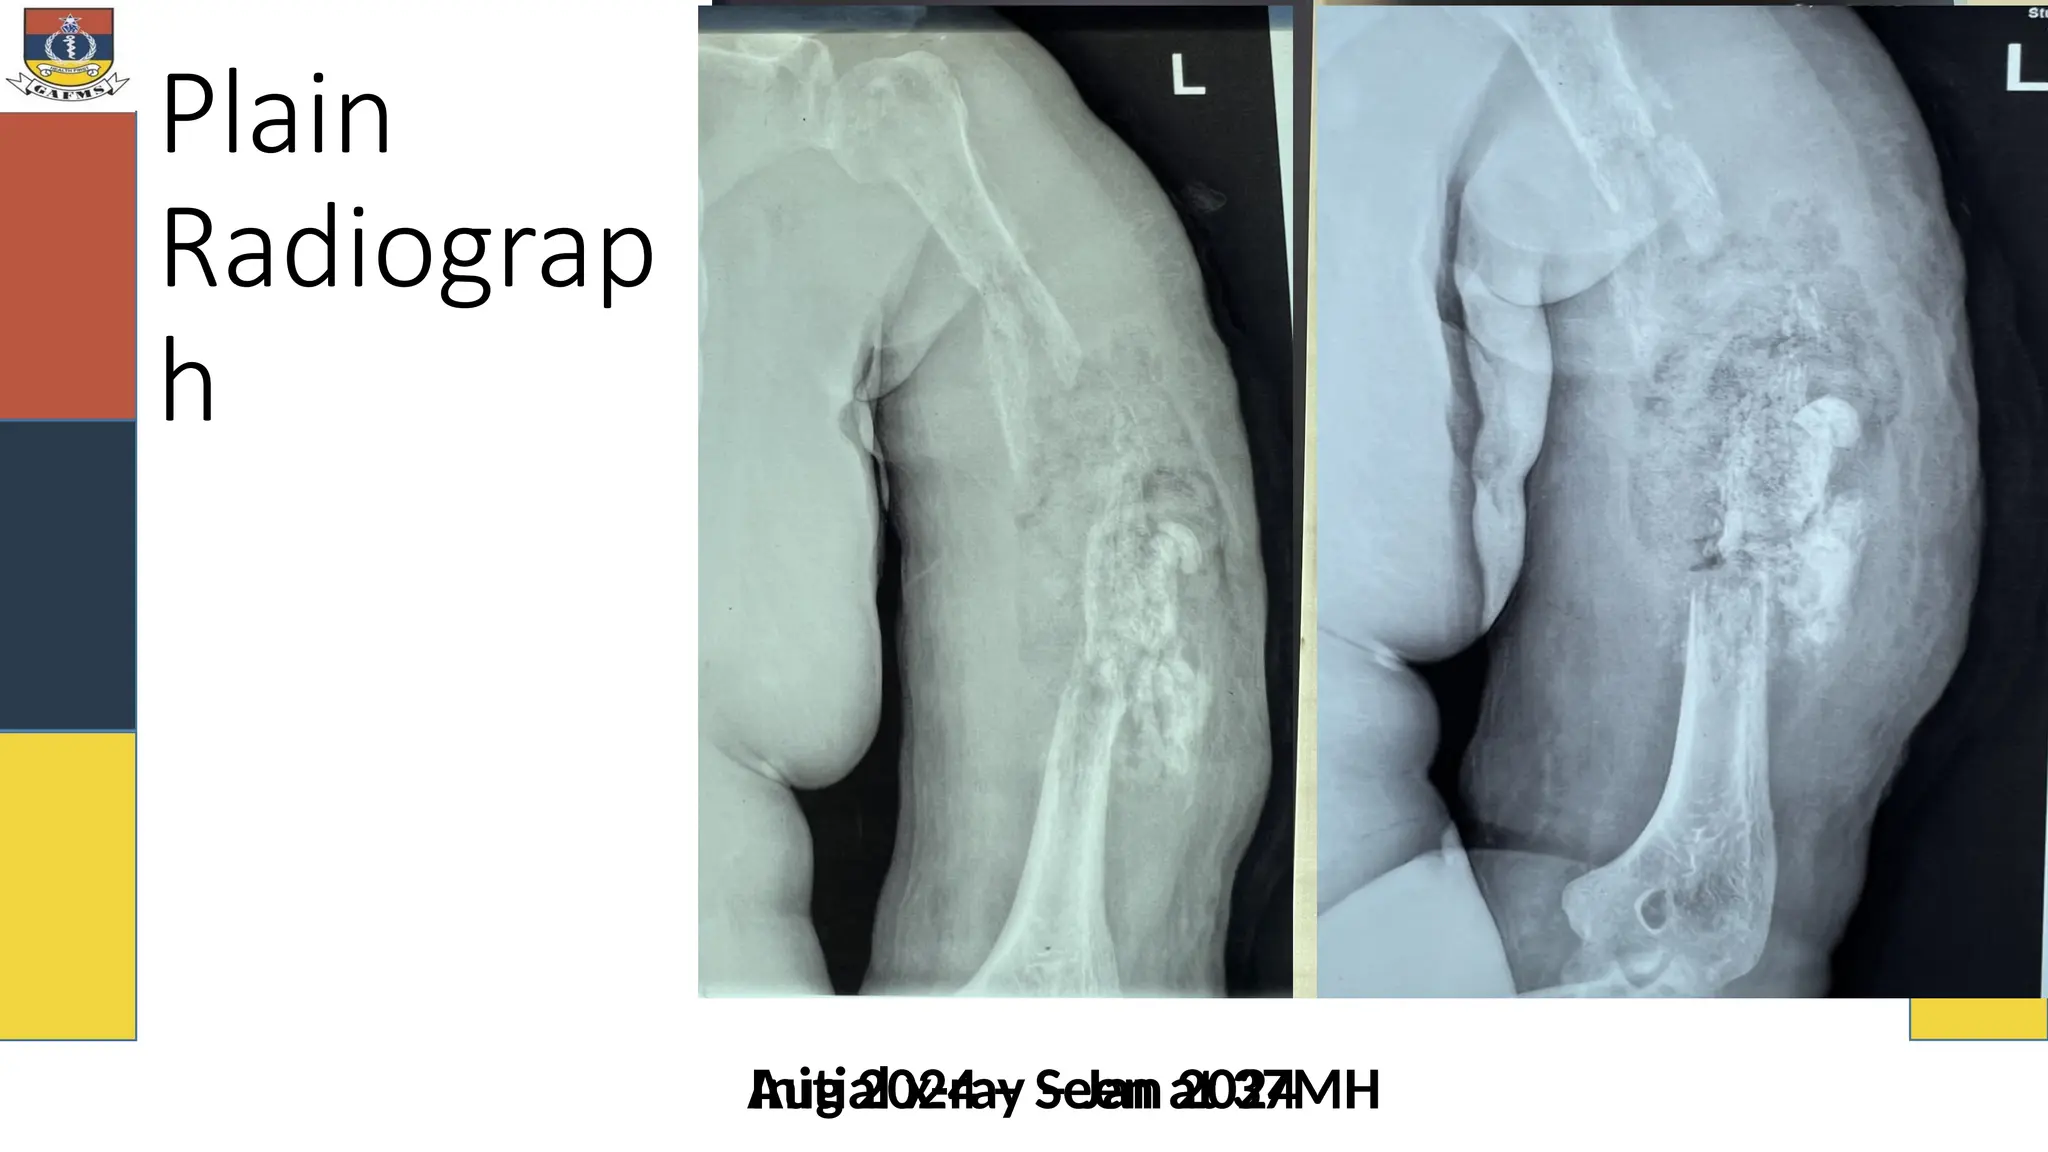

Plain

Radiograp

h

Initial x-ray – Jan 2024

Aug 2024 – Seen at 37MH